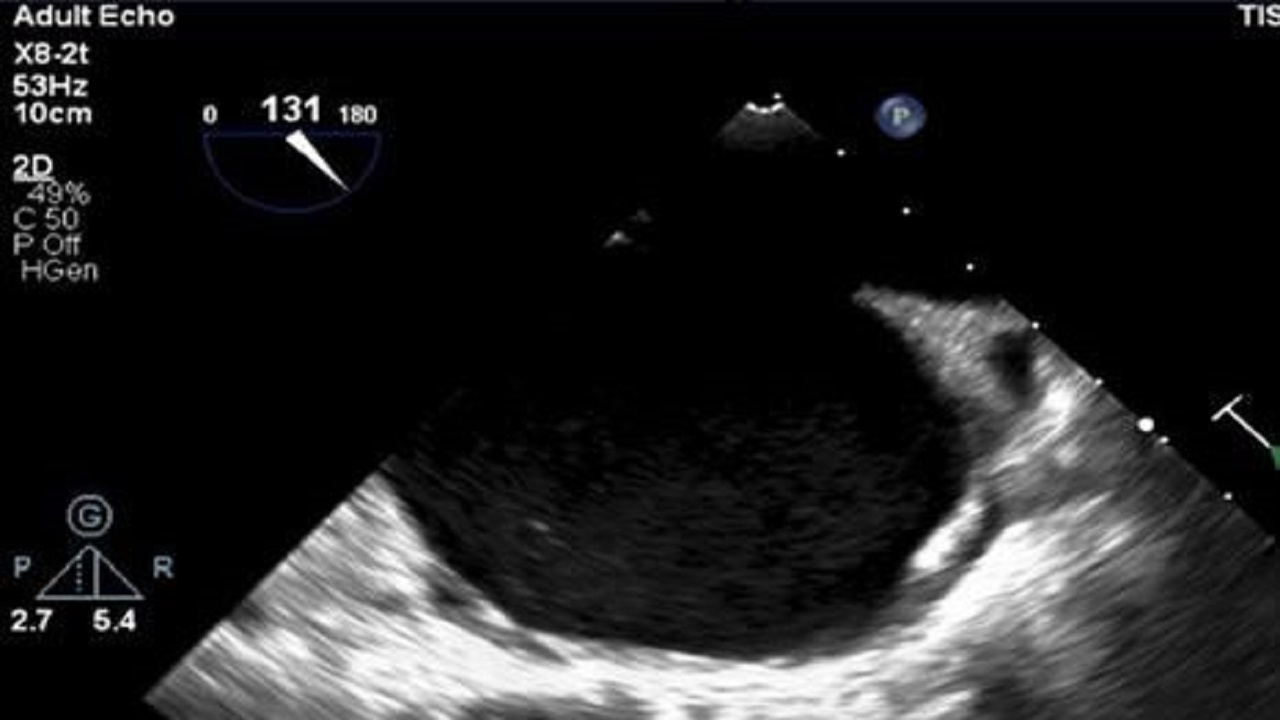

إنقاذ حياة مريضة حامل تعاني من القلب

منذ 3 سنة

0

1309